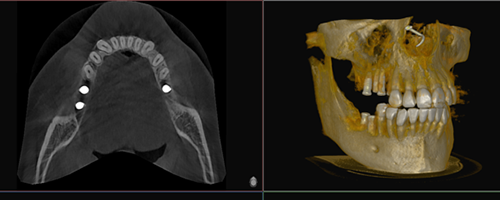

Bei biadent verbinden wir fortschrittliche Behandlungsmethoden mit höchster handwerklicher Präzision. Durch den Einsatz neuster Technologien garantieren wir Ihnen eine diagnostisch fundierte und therapeutisch exzellente Versorgung.